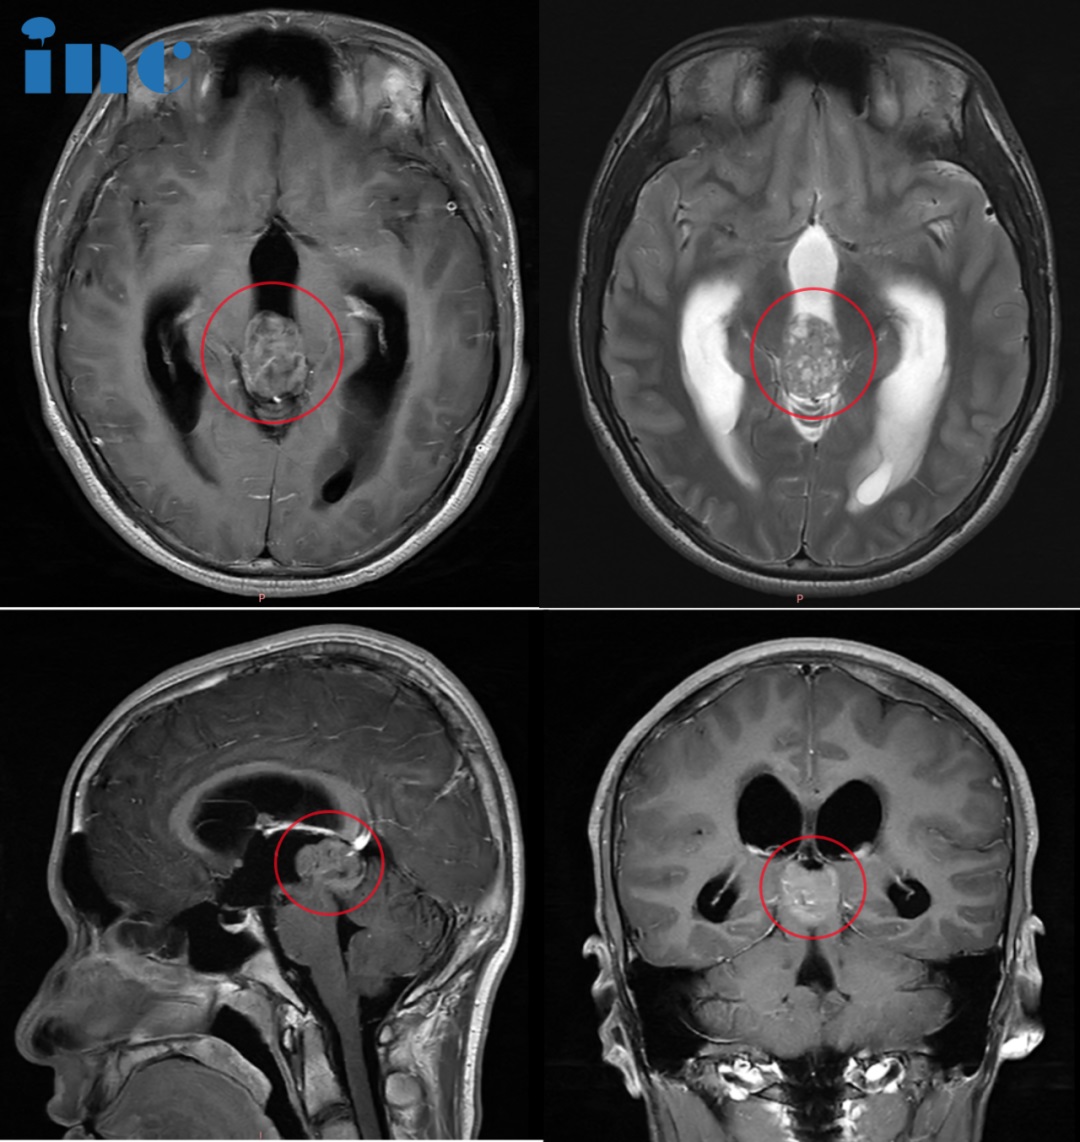

16岁少年——松果体占位性病变

“越早切除肿瘤对患者越有利,因为梗阻性脑积水可能危险。切除率将至少达到99%,甚至全切,他的预后会好。”

16岁少年霖霖6年前就因脖子不舒服查出松果体钙化,当时医生建议随访,无不同处理。2023年8月开始,霖霖又出现各种不适,眼睛胀痛、呕心想吐……10月初,不放心的父母又带着霖霖去医院进行核磁检查,医生只是建议多休息。症状虽然得到轻微缓解,但还是会时常感到不适。16岁的年纪,生龙活虎,有使不完的精力,热爱运动,阳光向上。而且处在人生的关键阶段,父母也不敢掉以轻心,然而就医的结果却还是建议保守治疗,且手术风险大。为了防止肿瘤进一步对孩子造成更大的伤害,少年的父母需做出选择,下一步该怎么办。无论作何抉择都决定着孩子余下人生的走向,他们需谨慎。

父母在网上查询之际得到巴教授10月底到天坛医院进行手术交流的信息,父亲拨通了INC国际神经外科的电话。恰巧他们此时正在北京,都很便利。咨询巴教授手术,一步先请教授评估:“这是一个明确的手术病例,而且手术相当紧迫,越早切除肿瘤对患者越有利,因为梗阻性脑积水可能危险。切除率将至少达到99%,甚至全切,他的预后会好。”在视频连线询问情况、观看影像资料后,巴教授进行了详细的量化评估。这样的回答也让霖霖一家有了新的希望和选择,他们坚定选择巴教授北京天坛医院的手术。

巴教授抵达北京天坛医院后为霖霖一家进行术前谈话。术前谈话谈什么?巴教授给他们详细介绍了手术过程、风险和预后,还特别解释了术中使用的手术入路等等。对于父母关心的手术风险,巴教授解释:“我做过很多同样的手术。他的肿瘤位于大脑枕叶和小脑之间。我们可以这样操作,就能在中间得到一点空间。因而,我们可以进入大脑深部,经过间隙进去,而不是穿过脑组织。这个手术不是较困难的。明天(10月31日)我也要为一个患儿做类似的手术,上次我在天坛也做了同样位置的手术。”